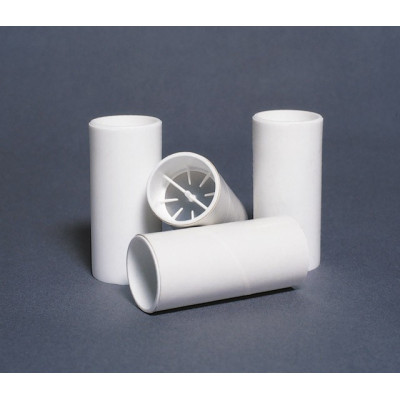

Safe-t-Chek One-Way Valve Mouthpieces

Safe-t-Chek mouthpieces adapt to all spirometers, peak flow meters and other PFT devices! Its innovative design virtually eliminates the threat of cross-infection. Patients worry about getting germs from others – now they can relax with Safe-t-Chek. The unique 8-point peripheral support creates a complete seal, as the valve closes completely if the patient attempts to inhale. This interrupts air flow, and helps to prevent the passage of airborne infectious particles. Keep your patients safe...with Safe-t-Chek!

- Very low air resistance

- Smooth design ensures patient comfort

- Disposable cardboard or flexible plastic models

- As the patient exhales, the Safe-t-Chek valve opens.